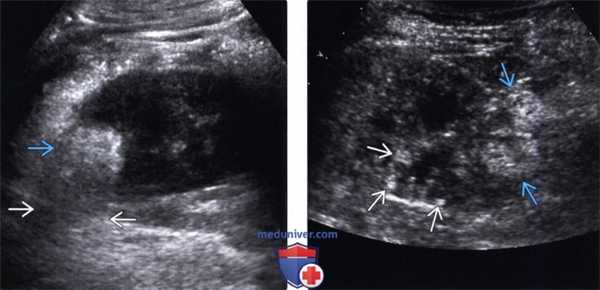

• Исследование в режиме серой шкалы:

о Классическая картина: четко определяемое, заметно гиперэхогенное образование по отношению к нормальной паренхиме почки с отсутствием акустической тени:

- Однако подгруппа АМЛ с минимальным содержанием жира обладает структурой от изо- до слегка гипоэхогенной; кроме того, у них отсутствует акустическая тень

- АМЛ с минимальным содержанием жира обычно гомогенные и изоэхогенные

о ПКР небольшого размера также может быть гиперэхогенным:

- АМЛ и ПКР невозможно отличить друг от друга на УЗИ

- Требуется дальнейшее исследование с помощью КТ, МРТ или биопсии

• Цветовая допплерография:

о Обнаружение псевдоаневризмы:

- Овоидные или округлые структуры, заполненные цветовым потоком, находящиеся внутри или рядом с АМЛ Цветовой поток имеет вид завихрения или в виде признака «инь-янь»

- Во время спектрального анализа шейки псевдоаневризмы обнаруживают классическую картину потока «из стороны в сторону»

• Энергетическая допплерография:

о Большинство АМЛ обладают «внутриопухолевой очаговой картиной»:

- Центральный внутренний поток, не распространяющийся к краям опухоли

о Напротив, большинство ПКР небольших размеров обладают смешанной периферической и проникающей картиной:

- Поток определяют в центре опухоли с распространением к ее краям/периферии

(Левый) На продольном ультразвуковом срезе визуализируется гиперэхогенная АМЛ в верхнем полюсе почки. Обратите внимание на незначительное заднее акустическое затенение.

(Правый) На продольном ультразвуковом срезе почки у пациента с туберозным склерозом визуализируется гиперэхогенная АМЛ с экзофитным ростом. Повышенная эхогенность коркового вещества почки сочетается с множественными мелкими гиперэхогенными очагами, представляющими собой более мелкие АМЛ.